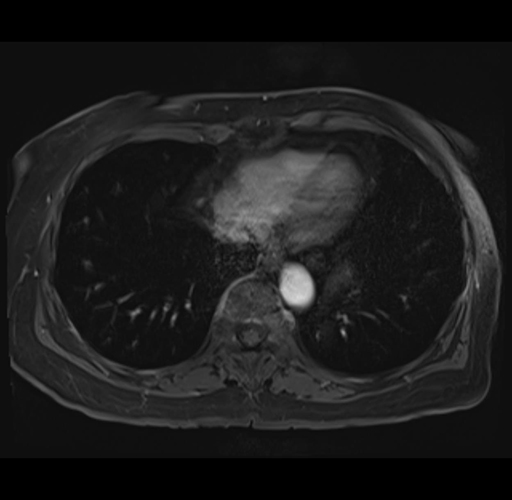

MRI T1